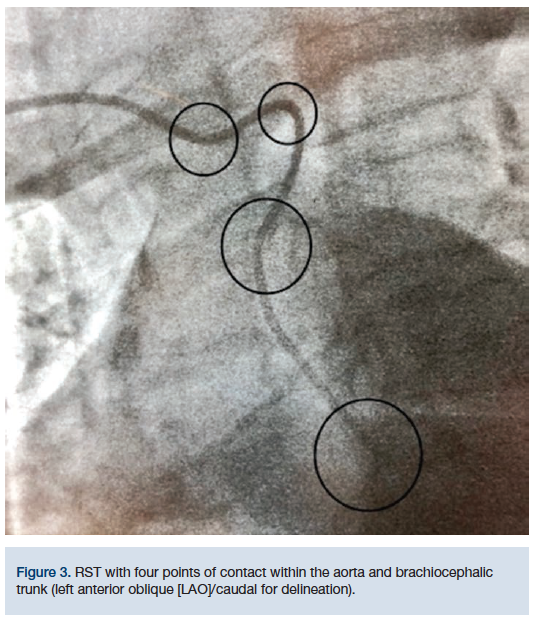

Independently or in combination, RST can make a radial procedure arduous. “Corkscrewing” of the right subclavian can prove to be extremely challenging for gaining access into the AA. Furthermore, it adds a level of difficulty cannulating the coronaries, on account of torque being transmitted into the tortuosity of the IA rather than the tip of the catheter. This occurs because there are several points of contact with the catheter and the brachiocephalic trunk (best delineated in the left anterior oblique [LAO]/caudal view) (Figure 3).